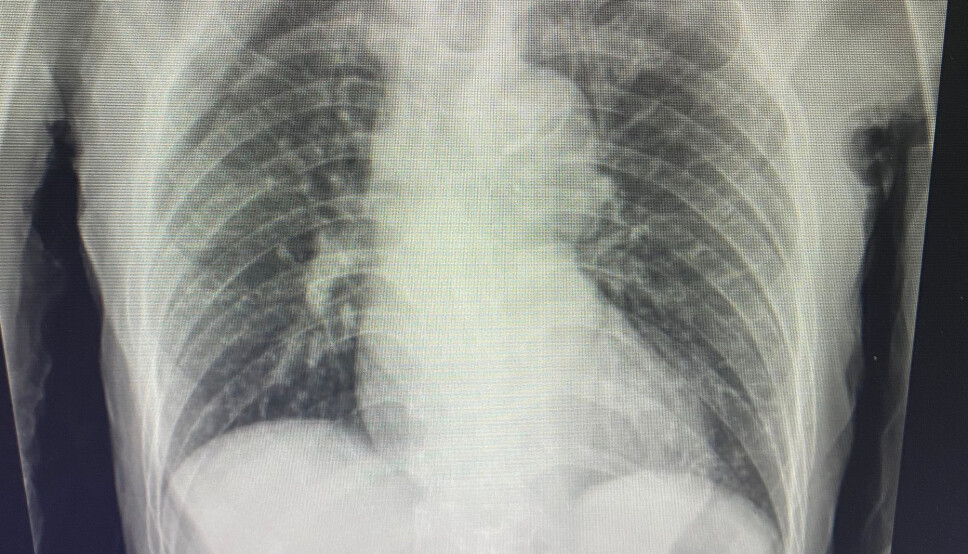

X-ray showing possible tuberculosis infection. A research team at NTNU have now managed to film the process of how the tuberculosis bacterium kills its host cell.